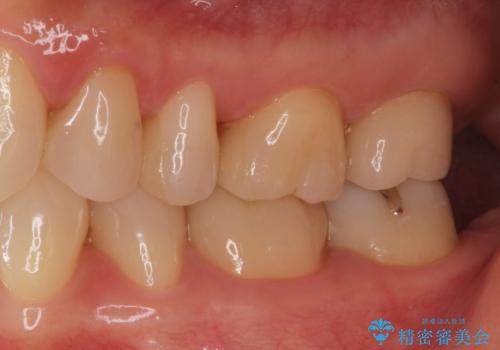

- ジルコニアクラウンスタンダード・仮歯 12.1万円 e-maxインレー・7.7万円費用は治療当時の料金となります

適合の良い詰め物、被せ物が入りました。